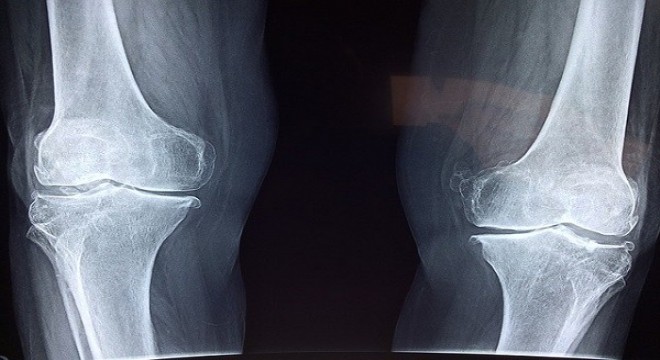

Kemik sağlığını korumak için K2 ve D3 vitamin desteği önemli

Araştırmalara göre; Türkiye’de 50 yaş üzeri her 2 kişiden 1’inde düşük kemik kütlesi, 4 kişiden 1’inde ise kemik erimesi görülüyor.

Kemik sağlığının korunması için kalsiyum önemli ancak tek başına yeterli değil. New Life Ürün Müdürü Uzm. Dyt. Sena Yazıcı Heyik “Beraberinde K2 vitamini takviye edilmezse vücuda alınan kalsiyum damarlarda birikerek, damar sertliğine yol açabilir. Bu da kalp krizi, inme gibi daha büyük sorunlara yol açabilir. Yapılan araştırmalar da kalsiyum takviyesi ile birlikte kullanılan K2 vitamini ve D vitamininin kemik sağlığında, tek başına kalsiyum takviyesi kullanımına göre çok daha etkili olduğunu gösteriyor. Bu yüzden kemik sağlığını korumak isteyenler için hem K2 hem de D3 vitamini içeren New Life Mena K2+D3’ü sunuyoruz” dedi.

K vitaminin 2 temel formu bulunduğuna dikkat çeken Sena Yazıcı Heyik, şunları söyledi: “Bunlardan biri K1 diğeri ise K2 vitaminidir. Her iki vitaminin de farklı görevleri bulunmaktadır. K1 vitamini kan pıhtılaşmasında rol oynarken K2 vitamininin böyle bir etkisi bulunmaz. K2 vitamini, yağda çözünebilen ve vücutta depolanan bir vitamindir. Emiliminin yüksek olabilmesi için yağlı besinlerle birlikte alınması gerekir. Mena K2+D3 kapsülleri ise zeytinyağı bazlı olduğundan ekstra yağlı besin tüketimine ihtiyaç duyulmaz. Bunun yanı sıra kalp ve kemik sağlığıyla ilgili 2 görevi bulunan K2 vitamini kalsiyum ile doğrudan bağlantılıdır. Besin ya da takviye yoluyla alınan kalsiyumun kemiklere bağlanmasını sağlayarak kemik mineral yoğunluğunun artırılmasına ve kemik erimesine karşı korunmaya yardımcı olur. Ayrıca vücuda alınan kalsiyumun damarlarda birikerek damar kireçlenmesi oluşumunu da engeller. Kısacası kalsiyumu doğru adrese teslim eder.”dedi.

Diz kapağında eklem kireçlenmesine dikkat

Çömelme ya da merdiven inip çıkma esnasında dizlerinizden gelen sesle ...